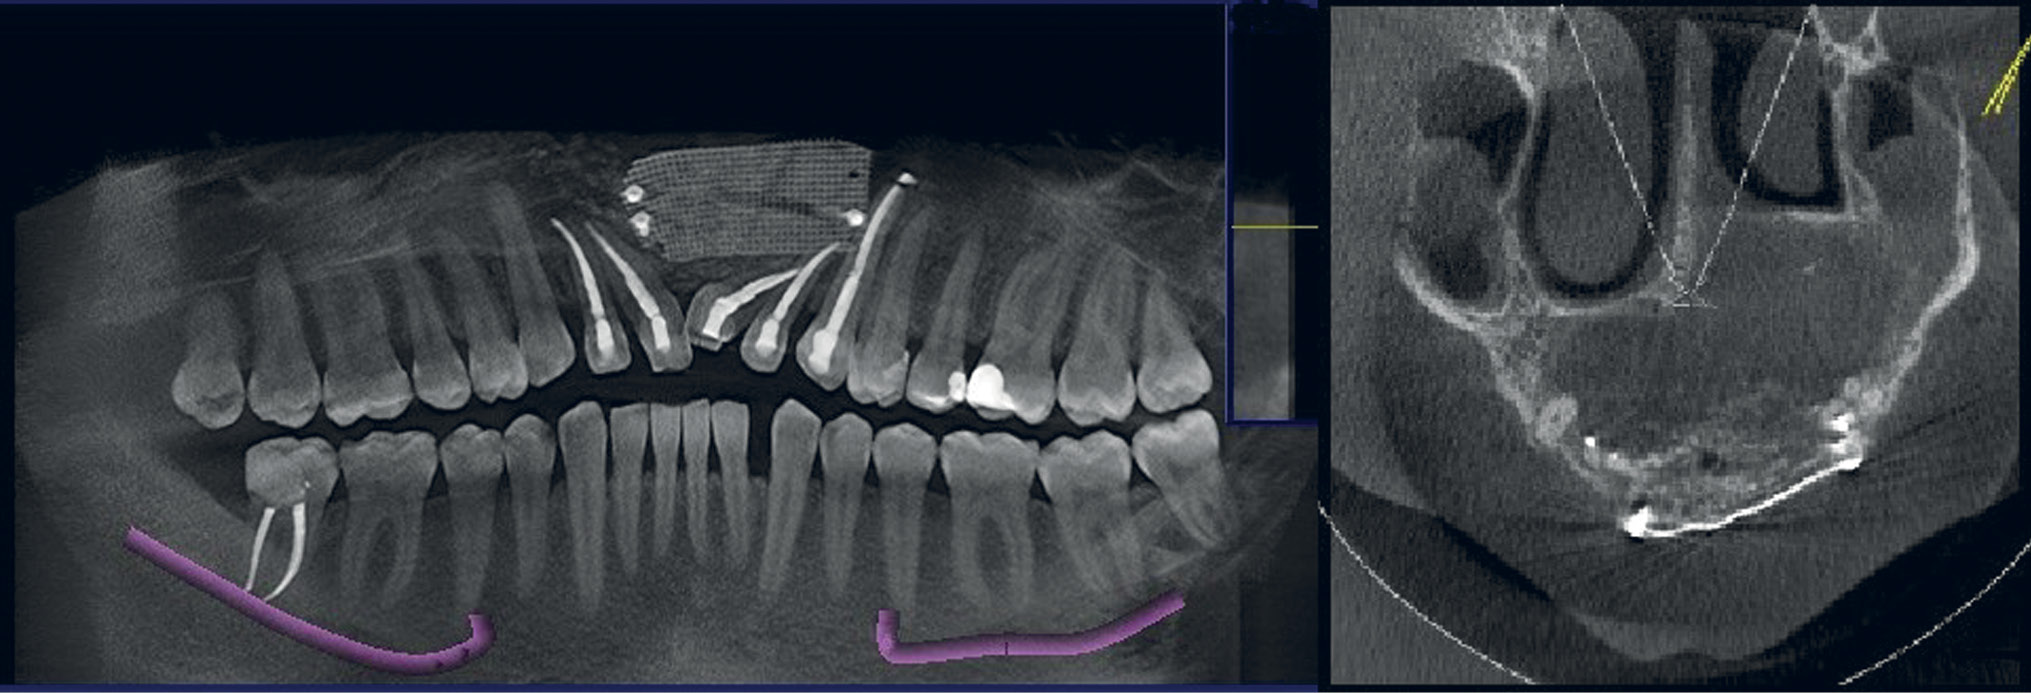

В период подготовки пациента к плановой операции было проведено предварительное эндодонтическое лечение зубов (1.2-2.3), которые прилежат корнями в полость кисты, корни зубов не лизированы. Данные о качестве эндодонтического лечения представлены на рис. 2.

Рис. 2. Пациент Д., 33 года: данные конусно-лучевой компьютерной томографии. Результат удовлетворительно проведенного эндодонтического лечения зубов 1.2-2.3, прилегающих к полости кисты, спустя 1 мес

Для исключения возникновения возможных инфекционно-воспалительных осложнений после эндодонтического лечения выжидали 1 мес. После контрольного исследования, подтвердившего качество эндодонтического лечения (см. рис. 2), было принято решение о выполнении оперативного вмешательства — удалении фолликулярной кисты с пластикой дефекта кортикальной пластинки отростка верхней челюсти титановой сеткой.